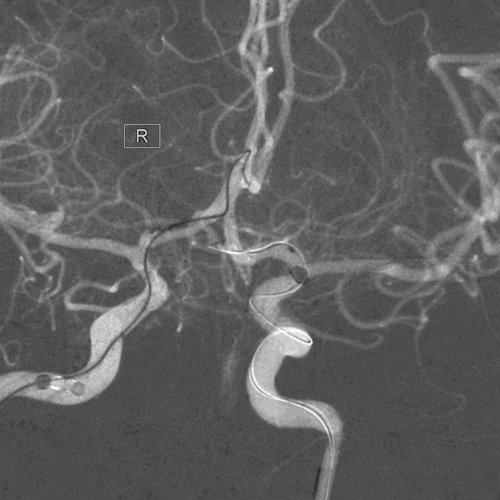

术前影像

左侧颈内动脉造影

右侧颈内动脉造影

双侧椎动脉造影

压颈造影及压颈3D

病例诊断:颅内多发动脉瘤

1.左侧大脑前动脉A1起始部未破裂动脉瘤(囊性)

2.右侧大脑前动脉A1起始部未破裂动脉瘤(夹层)